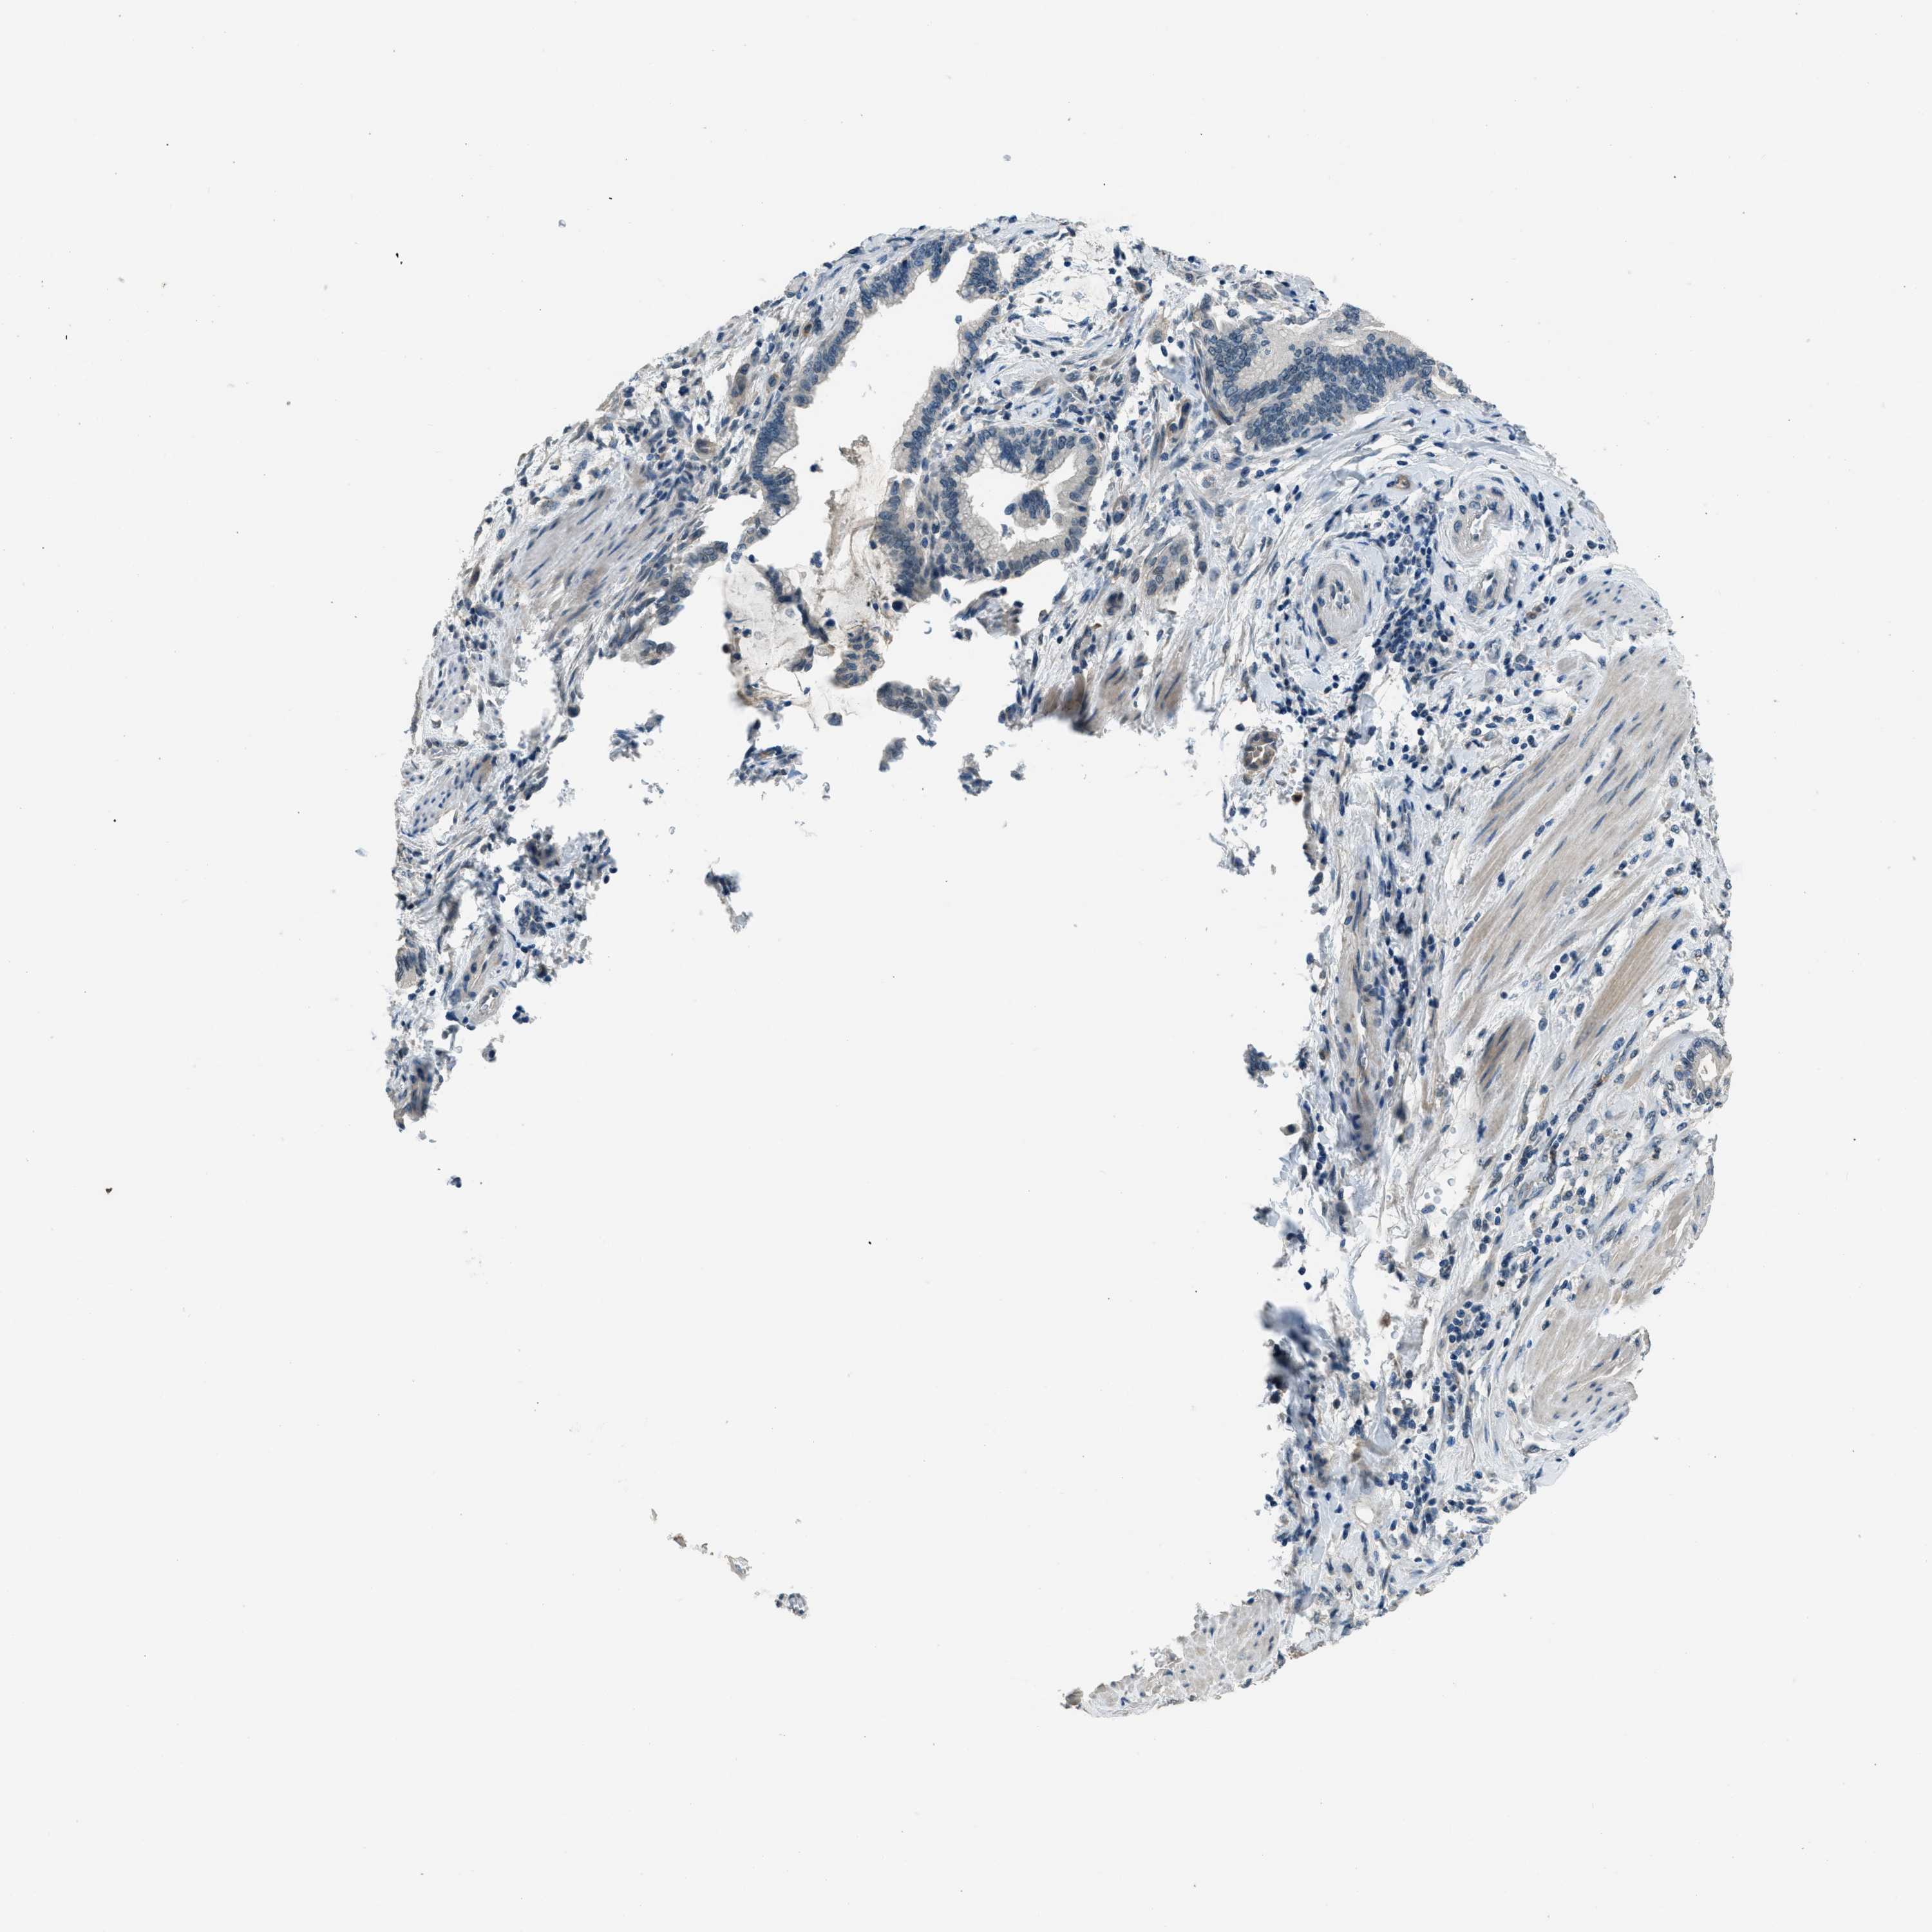

PANCREATIC CANCER - Protein expressioni

A mouse-over function shows sample information and annotation data. Click on an image to view it in a full screen mode. Samples can be filtered based on level of antibody staining by selecting one or several of the following categories: high, medium, low and not detected. The assay and annotation is described here.

Note that samples used for immunohistochemistry by the Human Protein Atlas do not correspond to samples in the TCGA dataset.

Antibody stainingi

Antibody staining in the annotated cell types in the current human tissue is reported as not detected, low, medium, or high, based on conventional immunohistochemistry profiling in selected tissues. This score is based on the combination of the staining intensity and fraction of stained cells.

Each image is clickable and will lead to virtual microscopy that enables deeper exploration of all samples and also displays staining intensity scores, fraction scores and subcellular localization as well as patient and tissue information for each sample.

Antibody HPA001818

Antibody CAB018352

Staining

High

Medium

Low

Not detected

Intensity

Strong

Moderate

Weak

Negative

Quantity

>75%

75%-25%

<25%

None

Location

Nuclear

Cytoplasmic/membranous

Cytoplasmic/membranous,nuclear

Adenocarcinoma, NOS